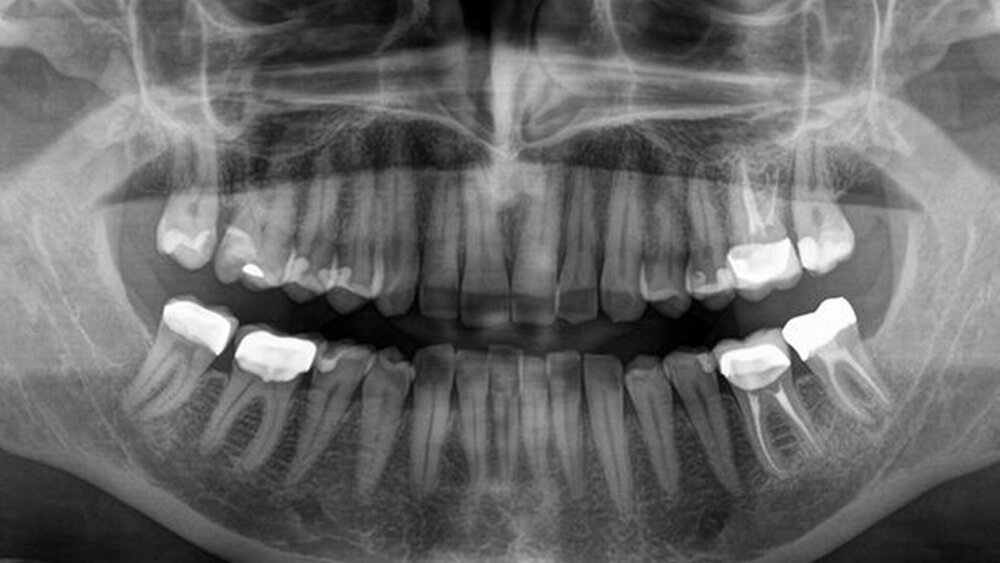

Die Geräte der Orthophos-Familie gehören zur neuesten Generation digitaler extraoraler Röntgengeräte. Sie bestechen durch eine außergewöhnliche Bildqualität und eine komfortable Bedienung.

Der Orthophos S beispielsweise ist sowohl in 2D als auch in 3D ein echter Allrounder seiner Klasse. Sein CsI-Plus-Sensor mit Autofokus-Funktion sorgt für zeichenscharfe Aufnahmen – auch in anatomisch schwierigen Fällen. Denn es sind anders als bei herkömmlichen Geräten keine manuellen Zwischenschritte notwendig, um den Kiefer des Patienten in allen Bereichen optimal in der Schärfe darzustellen. Dank der Autopositionierung mit dem patentierten Okklusalaufbiss werden Patienten ganz automatisch im Gerät ausgerichtet. Der Orthophos S verfügt über umfassende 2D-Programme für alle zahnmedizinischen Fragestellungen. Für den Einsatz in der Kieferorthopädie ist das Gerät optional mit einem Fernröntgenausleger verfügbar. Auch das 3D-Modul ist jederzeit nachrüstbar, um maximal flexibel zu sein.

Unter dem Motto „Echt.“ startet Dentsply Sirona zum 1. September seine neue extraorale Röntgen-Kampagne. Die Kampagne macht auf die zuverlässige Bildqualität beim Röntgen mit den Orthophos-Geräten aufmerksam.